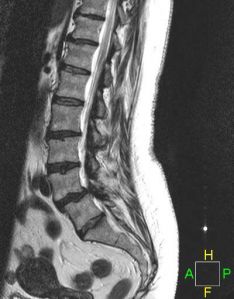

A complete history and physical exam are a necessary part of your medical work-up. Several diagnostic tests can be used including standard x-rays and other imaging such as an MRI or CT scan.

LUMBAR SPINAL STENOSIS

A complete history and physical exam are a necessary part of your medical work-up. Several diagnostic tests can be used including standard x-rays and other imaging such as an MRI or CT scan.

LUMBAR SPINAL STENOSIS